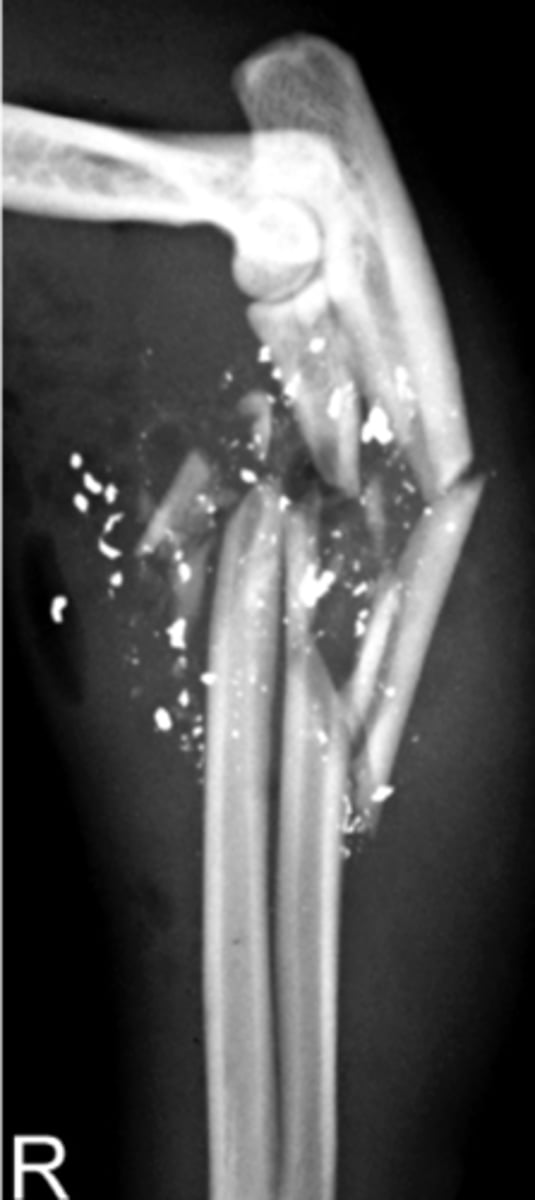

Comminuted fracture

What will most commonly cause a Comminuted fracture ?

Gunshot wound - lots of fragments

All Gun shot wounds will be ____ fractures?

Open